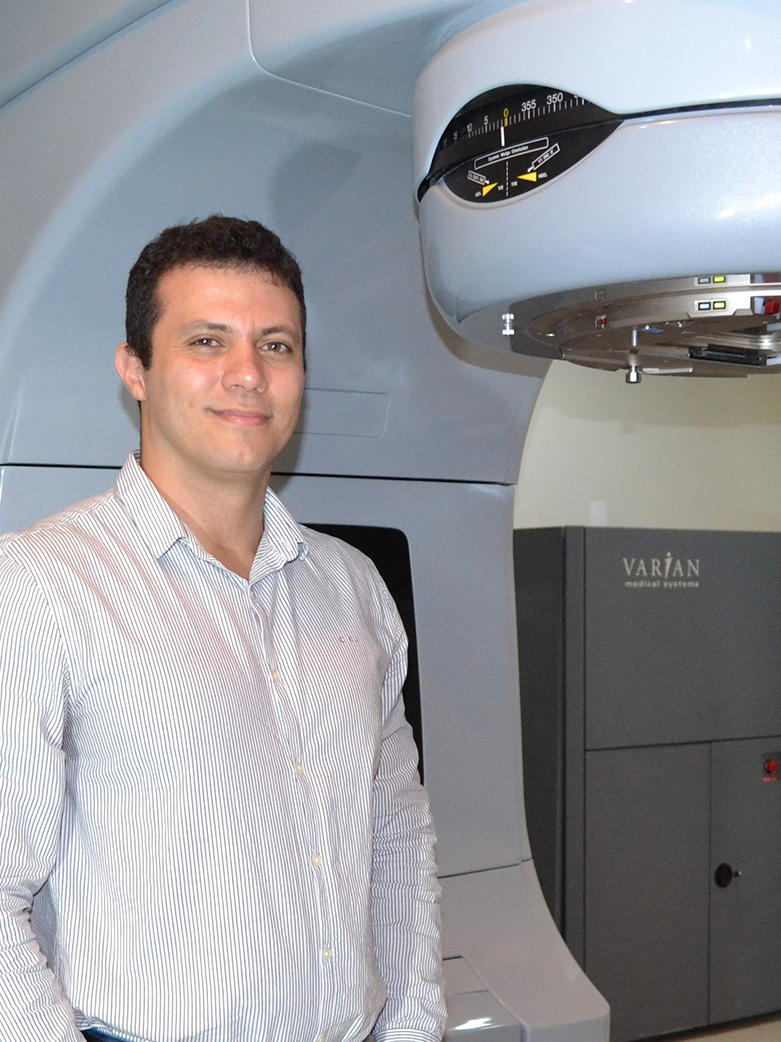

FERNANDO PJ

CEO